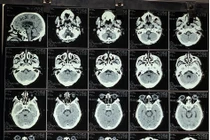

Đây là một ca máu tụ nội sọ kích thước và thể tích lớn trên nền bệnh nhân tăng huyết áp, béo phì... nếu không được phẫu thuật ngay hoặc quá trình vận chuyển không đảm bảo, tụt kẹt não dẫn đến tử vong.

Cả hai bệnh nhân đều trong tình trạng nguy kịch, rối loạn ý thức, huyết áp cao kịch ngưỡng. Dù bệnh nhân được cứu sống nhưng di chứng để lại vẫn rất nặng nề. Cần biết cách phòng tránh.

Khoảng 80% bệnh nhân bị xuất huyết não có tiền sử tăng huyết áp. Xuất huyết não thường gặp ở người cao tuổi có bệnh lý nền như tăng huyết áp và những bệnh nhân từng bị đột quỵ...

Dị dạng này là nguyên nhân gây xuất huyết não chủ yếu ở người trẻ và trẻ em với nguy cơ xuất huyết hàng năm là 2 – 4%. Tỉ lệ tử vong do xuất huyết là 10% và di chứng thần kinh là 30 – 50%.

Xuất huyết não do vỡ túi phình động mạch rất nguy hiểm, gây nguy cơ tàn phế và tỷ lệ tử vong cao. Một bệnh nhân 66 tuổi bị vỡ phình động mạch não trước đã được nút coil bảo toàn mạng sống.